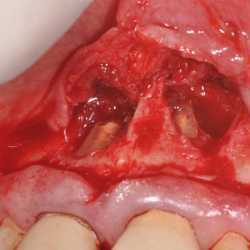

Inicio Especialidades Endodontia